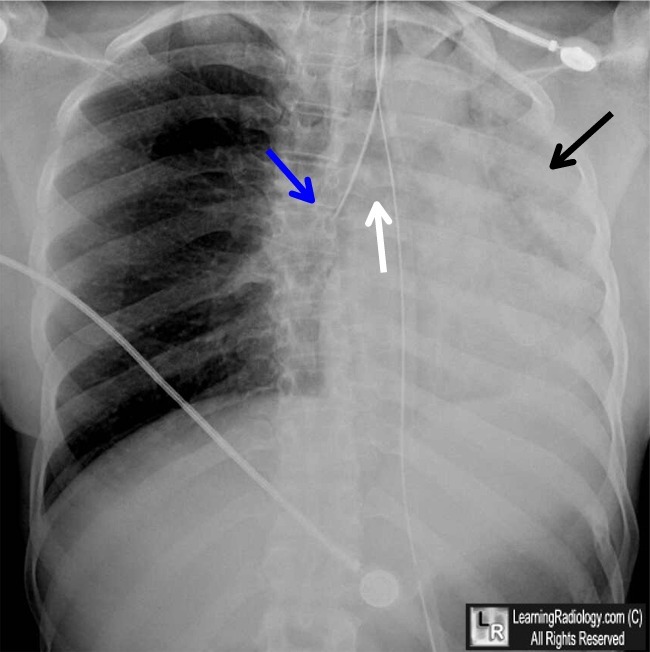

A patient is brought into ER after a major car accident. EMTs intubated and stablized patient. Dr. on staff orders a CXR. Explain the imaging. Also, what simple examination could be done to have accessed issue w/o CXR?

Left lung Atelectasis.

During intubation, breathing aparatis put in too far into respiratory tract into RIGHT BRONCHUS, siince compared to left bronchus, Right is more wide, straighter w/ trachea, & shorter.

Having air only to R. lung leaves left lung to collapse.

Easier solution to catch this: lung auscultation of both lungs during intubation